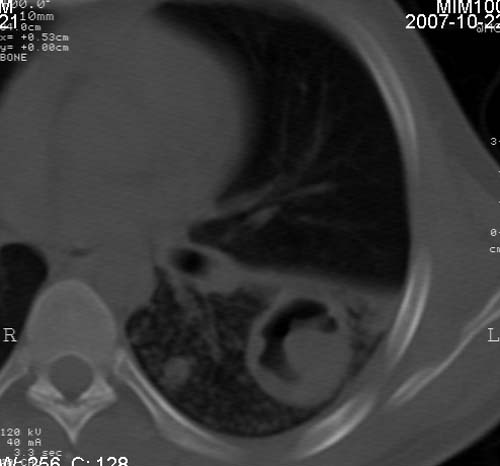

男,21岁,咳嗽、胸闷、乏力伴多汗二十余日、无明显发烧。患者一般情况好,为初三学生。

右肺上叶前段及左肺下叶多形性病变伴厚壁空洞,周边示树芽征.左肺下叶不张改变.

考虑;肺结核,不除外左肺下叶支气管内膜结核.

双肺继发性肺结核伴左侧空洞形成!不除外合并霉菌感染!(双肺多发病灶,左侧病灶形成空洞,并空洞内见壁结节。建议改变体位,观察空洞内结节情况,以便排除霉菌感染!)

左下肺实变能给出合理解释吗?